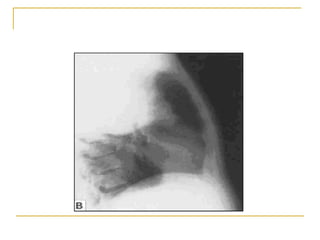

Radiografía lateral de torax. Bronconeumonía con atelectasia.

Caso 1: Radiografía lateral de tórax Descripción: Afectación de lóbulo superior derecho, con imagen radiopaca afectando el segmento anterior y posterior.  Presencia de broncograma difuso en región hiliar y apical, lobulación del hemidiafragma derecho. Diagnóstico:  Neumonía por Klebsiella